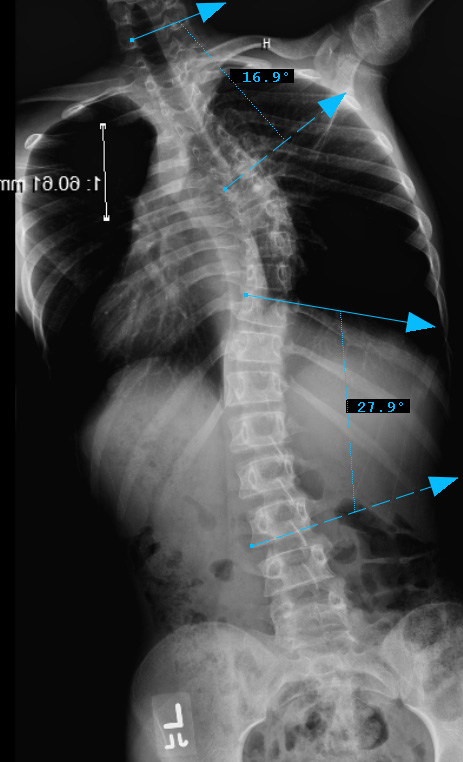

Preop LEFT Bend

thoracic curve non-structural, main thoracic curve major, Lumbar curves non-structural.

Lenke Type III describes a double major curve pattern. The main thoracic curve is considered the major curve as the greatest coronal plane deformity is present between T2 and the T11-12 disc. In Lenke Type III curves, the thoracolumbar/ lumbar spine is also considered structural. By definition, the thoracolumbar/ lumbar spine is structural if the deformity is greater than 25 degrees on side-bending radiographs or if the T10-L2 kyphosis is greater than 20 degrees in the sagittal plane. All lumbar and sagittal modifiers remain applicable in Lenke Type III curves. In general, both the MT and ThL/L curves are treated with instrumentation and fusion. The upper instrumented vertebra is between T2 to T4 depending on shoulder position and the lowest instrumented vertebra is either L3 or L4. The LIV should have near-neutral rotation, be at least one disc level below the apex of the lumbar curve and the disc below the LIV should be parallel or wedged open opposite to the side of the apex of the curve.